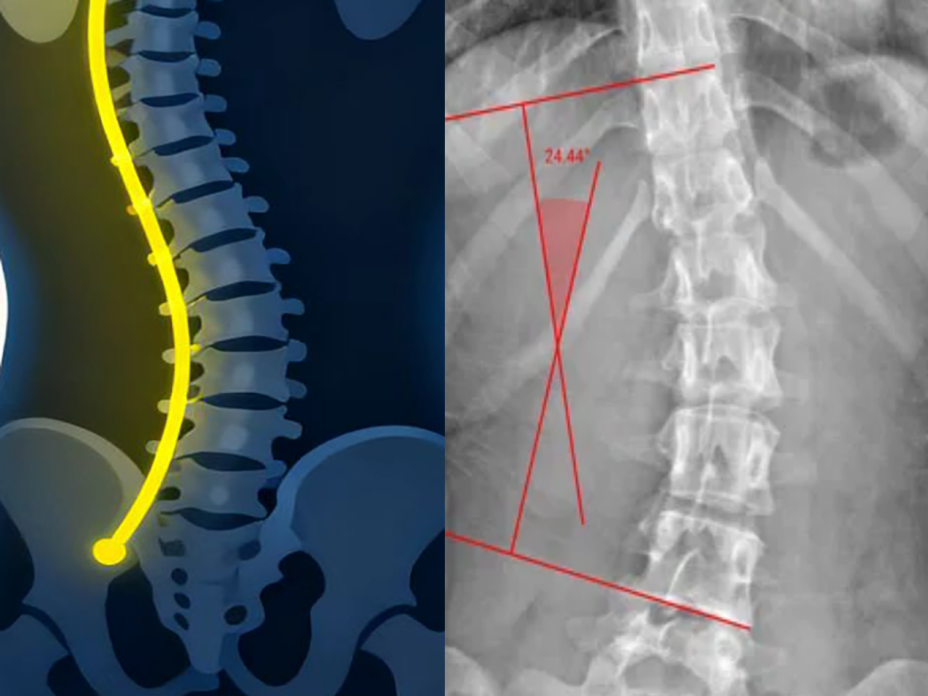

二、影像检查:诊断的金标准,剂量低到超乎您想象

当医生通过体格检查怀疑孩子有脊柱侧弯时,通常会建议拍一张脊柱全长的X线片,这是诊断和评估脊柱侧弯的“金标准”。医生通过测量X线片上的“Cobb角”来判断侧弯的严重程度。您可以把它想象成衡量脊柱“弯了多少度”的量角器。测量时,医生会先在脊柱X线正位片上找到弯曲弧度最明显的上下两个椎体,沿着上方椎体的上缘和下方椎体的下缘各画一条线,然后再画出这两条线的垂直线,最后量出这两条垂线之间的夹角——这就是Cobb角。一般来说,角度超过10度可以诊断为脊柱侧弯,25~45度可能需要佩戴支具,超过45度则可能需要考虑手术治疗。

图2 版权图片 不授权转载